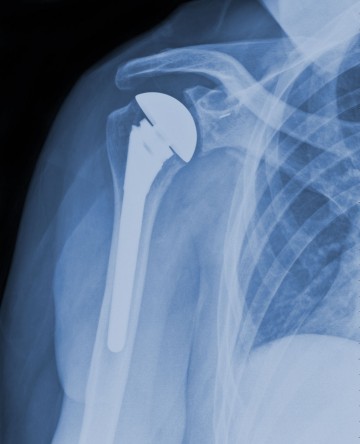

The joint replacement specialist treats disorders related to joints. Almost any joint in the musculoskeletal system can be damaged. Damage can result from injury, aging or metabolic disorders such as rheumatoid arthritis. Treatment may include rest, physical therapy, injections and joint replacement. The most commonly replaced joints are the knee. Hip and shoulder. Certain Wellington physicians specialize in replacing specific joints. All are skilled with the most current techniques for diagnosis and treatment.